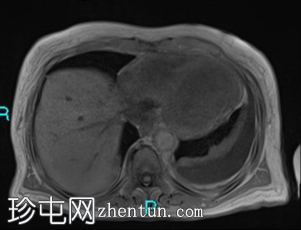

轴位T1加权像

同相位

胰腺钩突附近可见边界不清的肿块,T2加权像呈不均匀中等信号,弥散受限明显。肿块大小为4.1 x 5 x 3 cm(前后径 x 横径 x 头尾径)。伴有胰管扩张,直径约6 mm。

肝脏可见多个大小不一的可疑病灶(从亚厘米级到2厘米不等)。T2加权像呈高信号,弥散受限明显。

双侧胸腔积液,左侧较多。